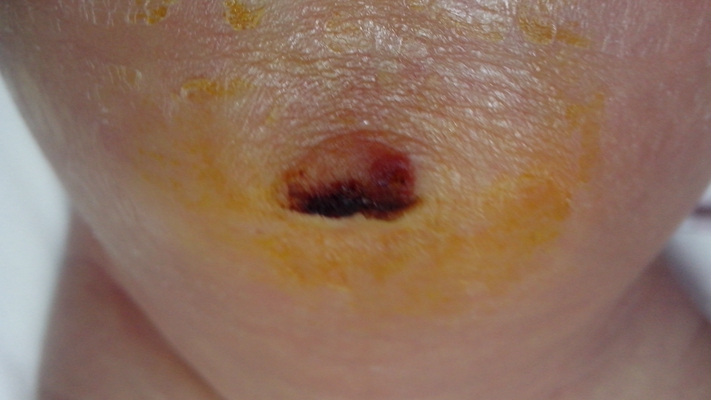

臍疝圖片

嬰兒臍疝

嬰兒臍疝

嬰兒臍疝

嬰兒臍疝

嬰兒臍疝